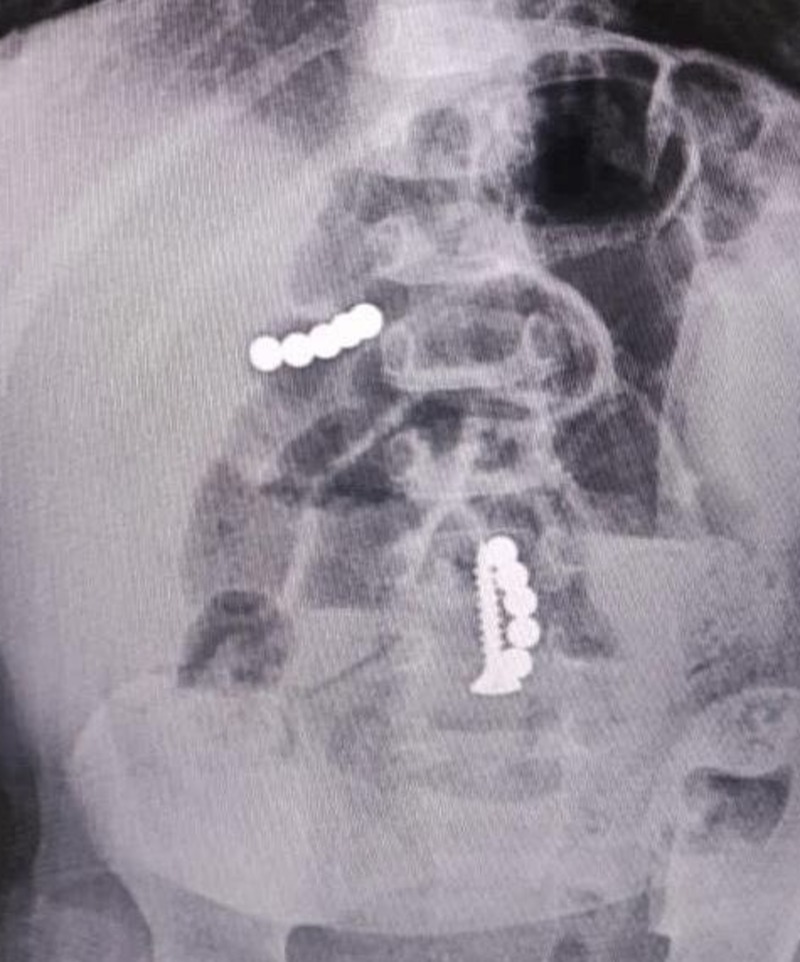

Хирурги получили исключительное право на способ лечения травм спинного мозга с восстановлением его функций конъюнгатом ПЭГ-хитозана. Срок действия патента — до 2042 года.

Как пояснил один из разработчиков Михаил Лебенштейн-Гумовски, это химическая смесь двух компонентов, которые взаимно усиливают друг друга. Экспериментальный гель помогает восстанавливать поврежденную структуру важнейшего органа.

Разработанная методика стала прорывом в области спинальной нейрохирургии. Способ лечения введут в клиническую практику для пациентов с травмами спинного мозга.